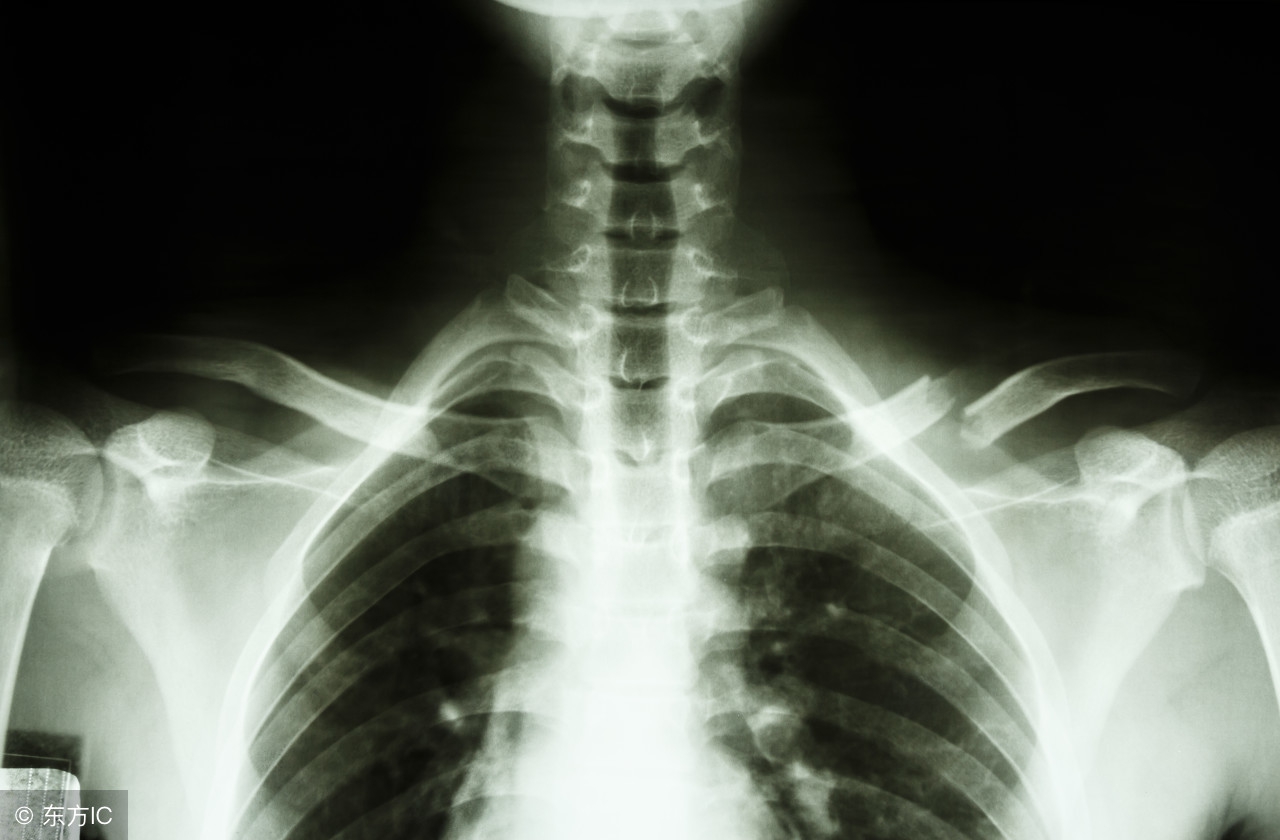

三、怀疑锁骨骨折了,需要做哪些检查?

医生会询问患者或者患儿详细的受伤病史,同时辅助查体,必要时会给你安排X线检查明确骨折的类型以及严重程度。

对于两岁的小孩,发生锁骨“青枝骨折”的可能性较大,X线可以帮助我们确诊!